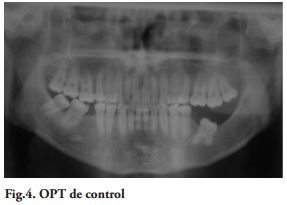

En la ortopantomografía (OPT) se observa una masa radiopaca compacta de 3,6 cm. x 3 cm. de alto, rodeada de zona radiolúcida fina. El primer molar inferior izquierdo está retenido por debajo de la masa mineralizada. Los molares superiores contactan con dicha masa (Fig. 2).

En el seguimiento de control del paciente, se realizó una OPT a los 2 años, que muestra una correcta reparación ósea y al primer molar inferior izquierdo en una posición avanzada de erupción (Fig. 4).